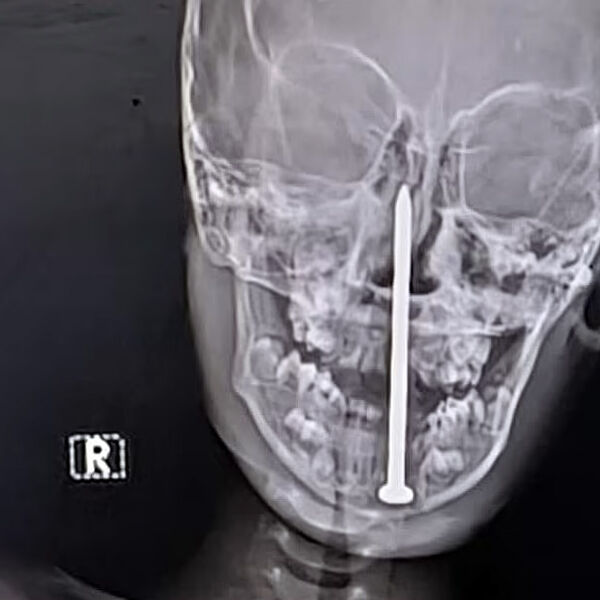

Семилетний мальчик из штата Раджастан перенес сложную нейрохирургическую операцию, во время которой врачи извлекли гвоздь длиной семь сантиметров из его мозга, пишет Daily Mail.

По данным местных СМИ, инцидент произошел, когда мальчик играл рядом со строительной площадкой, где споткнулся и упал носом на гвоздь. Его срочно доставили в больницу в Джайпуре, сделали компьютерную томографию и обнаружили, что инородный предмет почти на пять сантиметров проник в мозговую ткань.

Хирургическая бригада под руководством доктора Санкета Шармы провела более чем четырехчасовую операцию по удалению гвоздя. По словам врачей, чудом затронутыми оказались только лобные доли мозга, отвечающие в основном за когнитивные функции, а не за жизненно важные центры.

После операции ребенок находится в стабильном состоянии, хотя его перевели в отделение интенсивной терапии для дальнейшего наблюдения. Врачи выражают осторожный оптимизм относительно его полного восстановления.